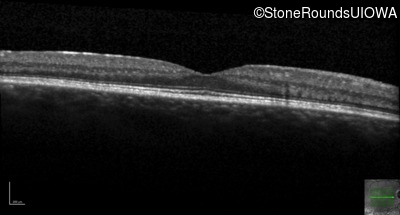

Optical Coherence Tomography - Right - 20/20 -3

Exemplar / OCT Stack

Optical Coherence Tomography - Right - 20/20 +1